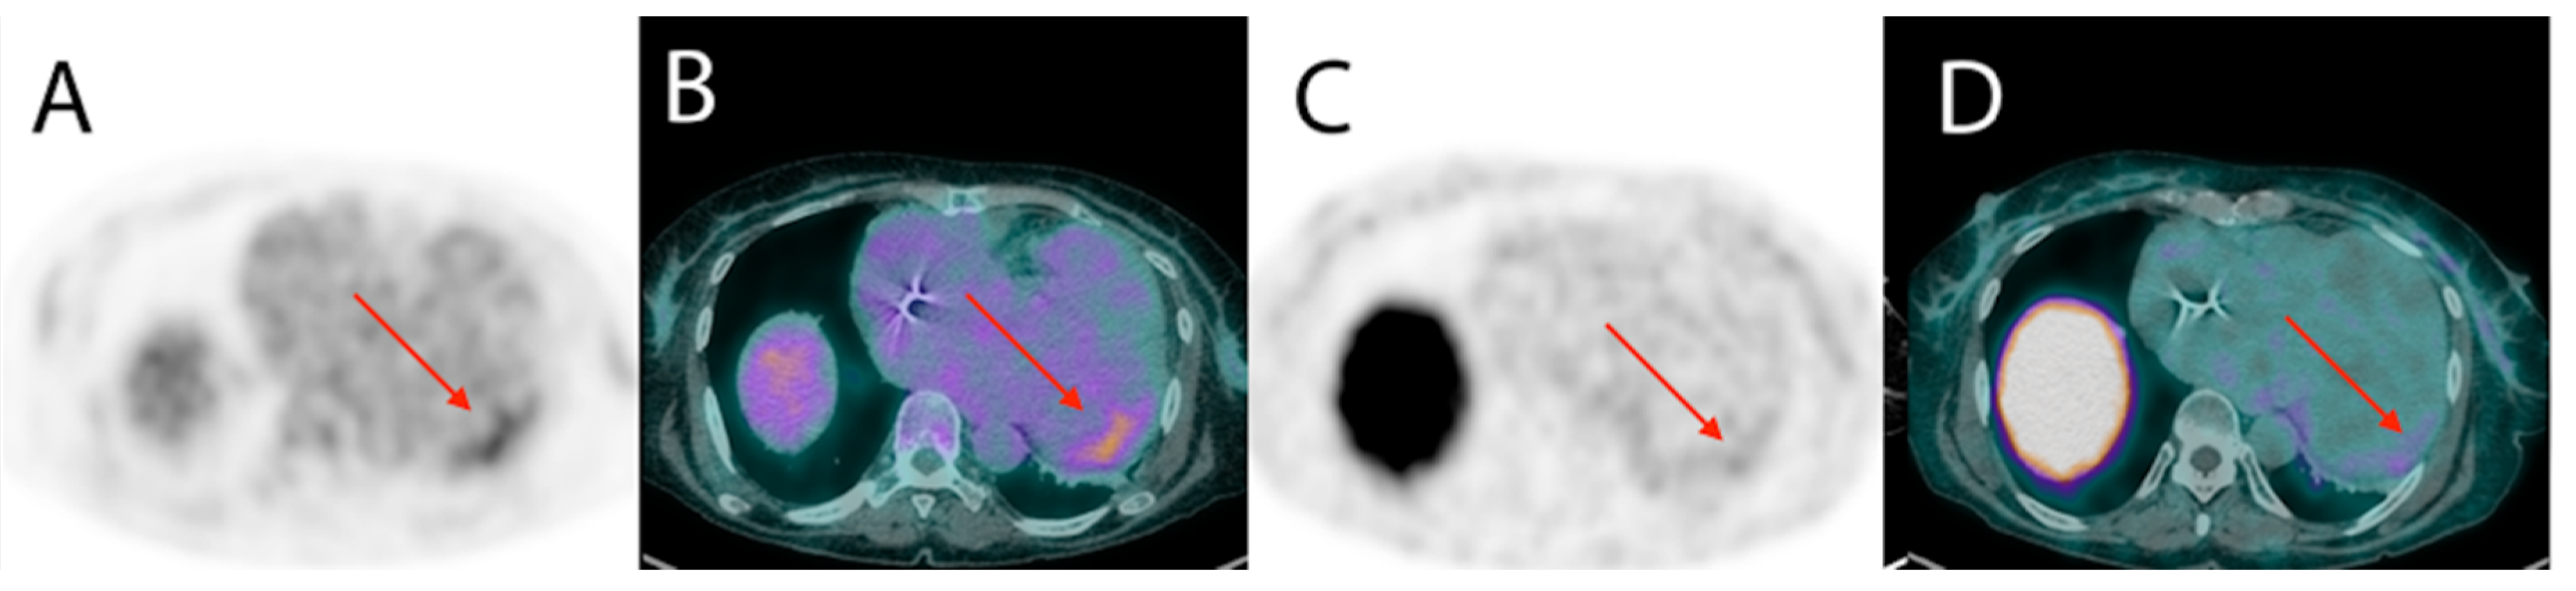

- James, O.G.; Christensen, J.D.; Wong, T.Z.; Borges-Neto, S.; Koweek, L.M. Utility of FDG PET/CT in inflammatory cardiovascular disease. Radiographics 2011, 31, 1271–1286. [Google Scholar] [CrossRef]

- Blankstein, R.; Osborne, M.; Naya, M.; Waller, A.; Kim, C.K.; Murthy, V.L.; Kazemian, P.; Kwong, R.Y.; Tokuda, M.; Skali, H.; et al. Cardiac positron emission tomography enhances prognostic assessments of patients with suspected cardiac sarcoidosis. J. Am. Coll. Cardiol. 2014, 63, 329–336. [Google Scholar] [CrossRef]

- Garg, G.; Cohen, S.; Neches, R.; Travin, M.I. Cardiac (18)F-FDG uptake in chagas disease. J. Nucl. Cardiol. 2016, 23, 321–325. [Google Scholar] [CrossRef]

- Shapiro, H.; Meymandi, S.; Shivkumar, K.; Bradfield, J.S. Cardiac inflammation and ventricular tachycardia in Chagas disease. HeartRhythm Case Rep. 2017, 3, 392–395. [Google Scholar] [CrossRef] [PubMed]

- Moll-Bernardes, R.J.; de Oliveira, R.S.; de Brito, A.S.X.; de Almeida, S.A.; Rosado-de-Castro, P.H.; de Sousa, A.S. Can PET/CT be useful in predicting ventricular arrhythmias in Chagas Disease? J. Nucl. Cardiol. 2020, 1–4. [Google Scholar] [CrossRef] [PubMed]